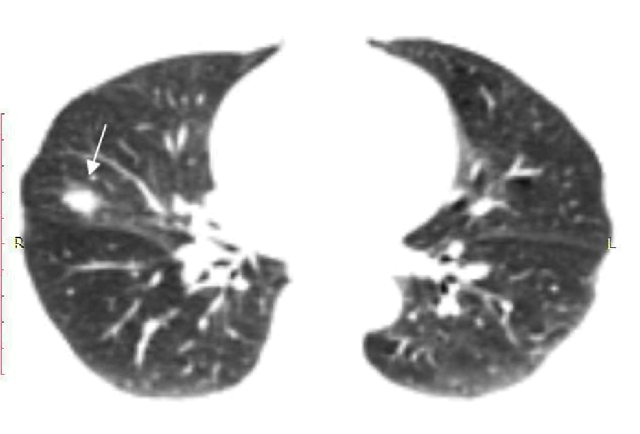

Дыхательная гимнастика при пневмосклерозе: техника и советы